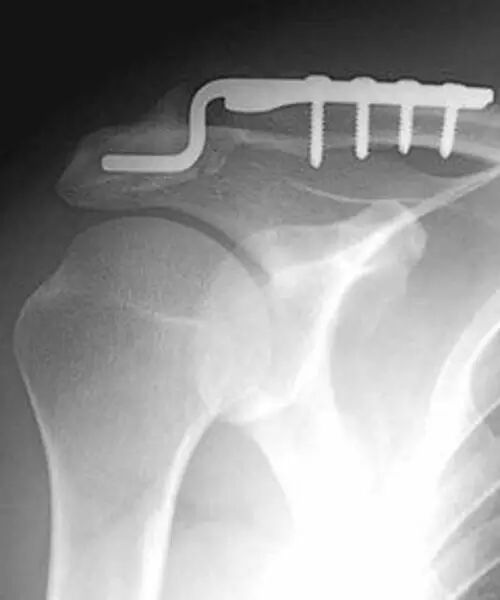

以下是锁骨钩钢板固定: